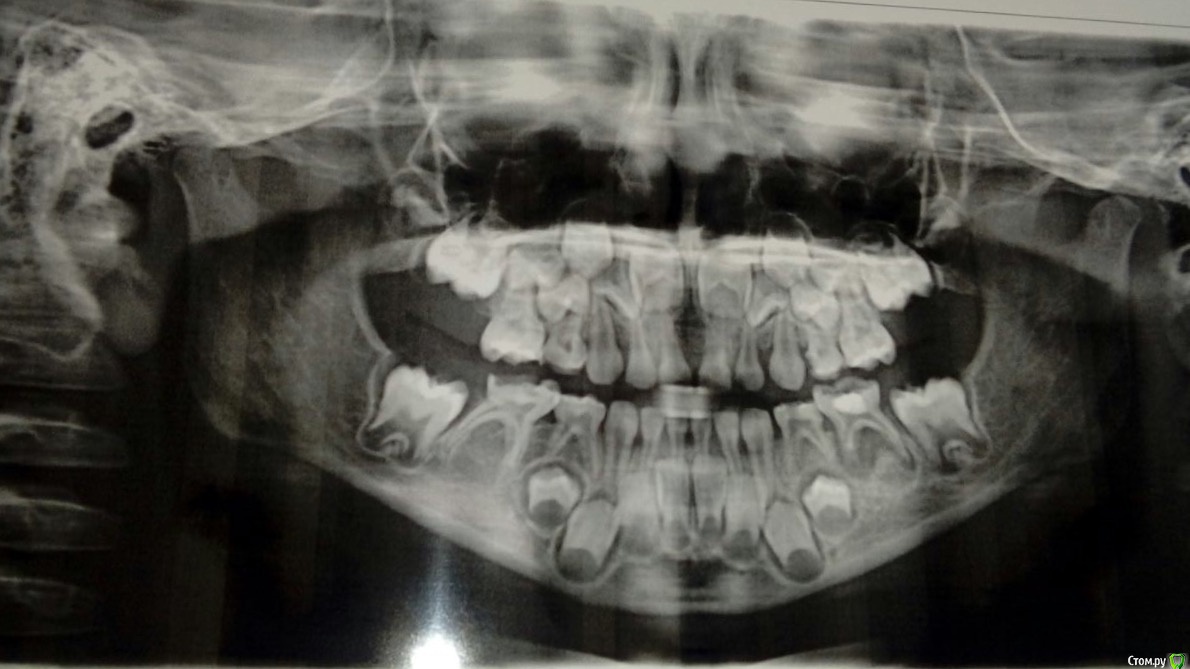

Алеся1983 Опубликовано 31 августа, 2017 Поделиться Опубликовано 31 августа, 2017 Добрый день! Ребёнку недавно исполнилось 6 лет! Заболел зуб, пошли к стоматологу, решили сразу лечить все зубы. Сделали панорамный снимок, а нам, у вас нет зачатков постоянных зубов нижних 5 и 7. А у нас как раз проблемный 5 зуб, есть немного воспаление. Очень расстроены! Уже дома, рассматривая снимок, мне показалось, что 1 пятый зачаток вроде есть, просто слабо выражен! Я конечно могу ошибаться, но очень хочется верить, что он есть! Если же зачатков все же нет, какое лечение в будущем нам необходимо. Буду благодарна за консультацию, спасибо! Ссылка на комментарий

Brigita Опубликовано 31 августа, 2017 Поделиться Опубликовано 31 августа, 2017 к сожалению, доктор прав. Зачатков нет Ссылка на комментарий